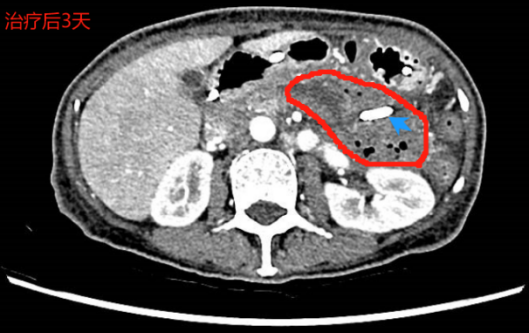

术后四天,团队通过

左图术后4天,可见大量坏死物堵住支架,“双支架”发挥重要作用;右图术后4周,支架、营养管位置良好,包裹性坏死腔内新鲜肉芽组织